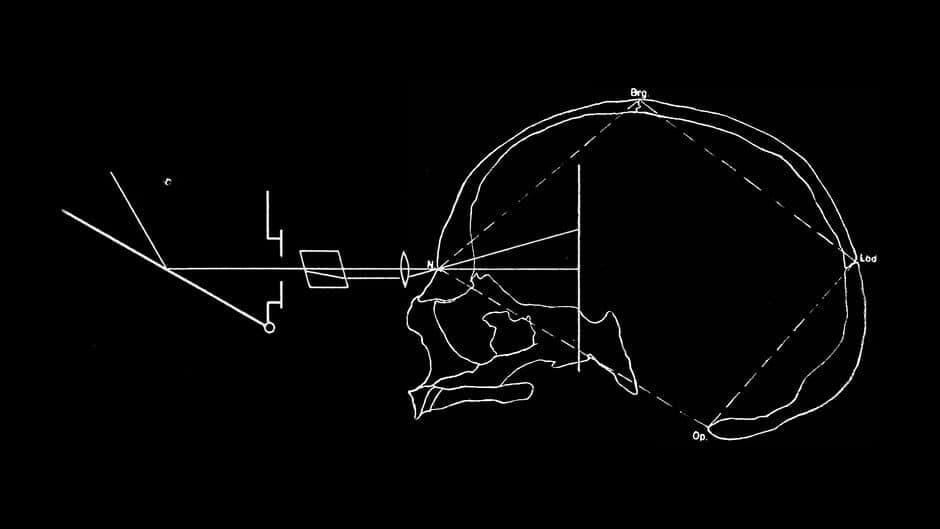

Asterion (noun)

II. (Anatomy) A point on the exterior of the skull.